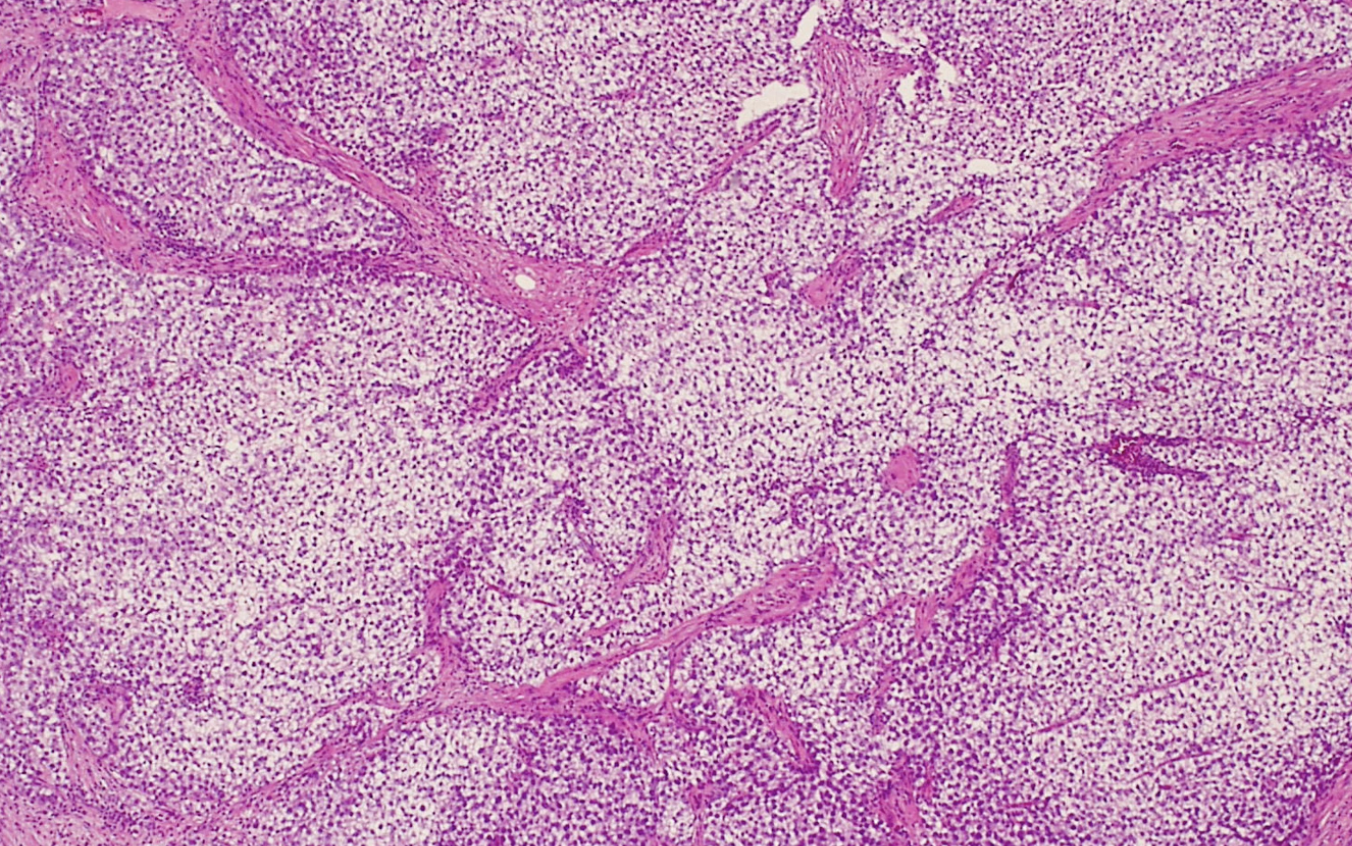

Testicular Lymphoma

Lymphoma